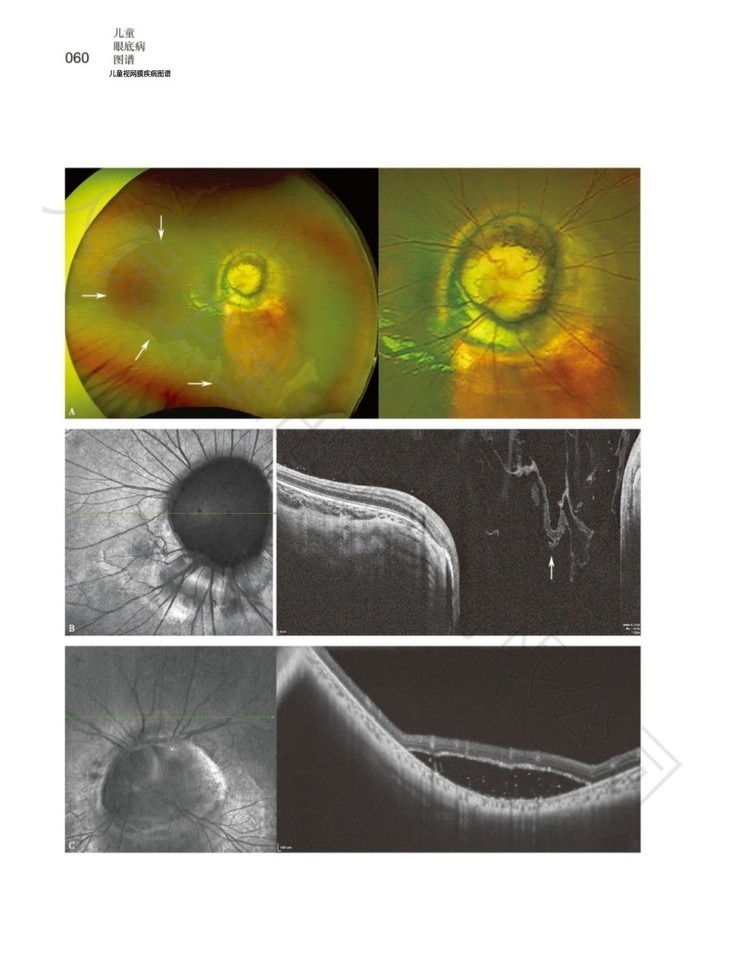

本书为儿童眼底病图谱类书籍。收集了中山大学中山眼科中心多平台积累的数百例典型小儿眼底疾病,其中不乏各类罕见病、以及常见疾病的少见表现。本书对纷繁复杂的小儿眼底疾病进行了科学的分类及介绍,并提供了大量高质量、特征性的疾病图片,全方位展示了相关疾病的特征,是全面、系统、直观认识小儿眼底疾病的不可多得的参考书。

3. 直观易懂:以直观、典型、多模式的图谱形式展现儿童眼底病的临床表现、诊断及治疗,更易懂。

4. 全面系统:系统介绍儿童眼底病的图书极少。而本书在系统性介绍各类小儿眼底病的同时,对疾病相关的图谱进行了细致的剖析,全方位展示了相关疾病的特征。